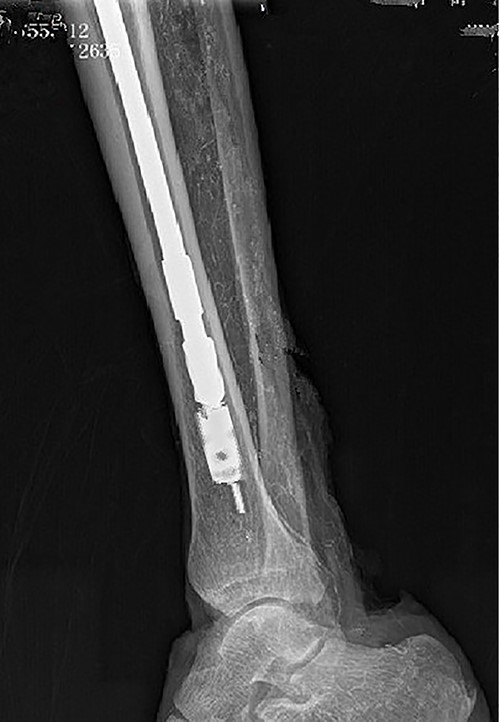

Intraoperative X-ray showing a drill used along a guide needle to ream the medullary cavity.